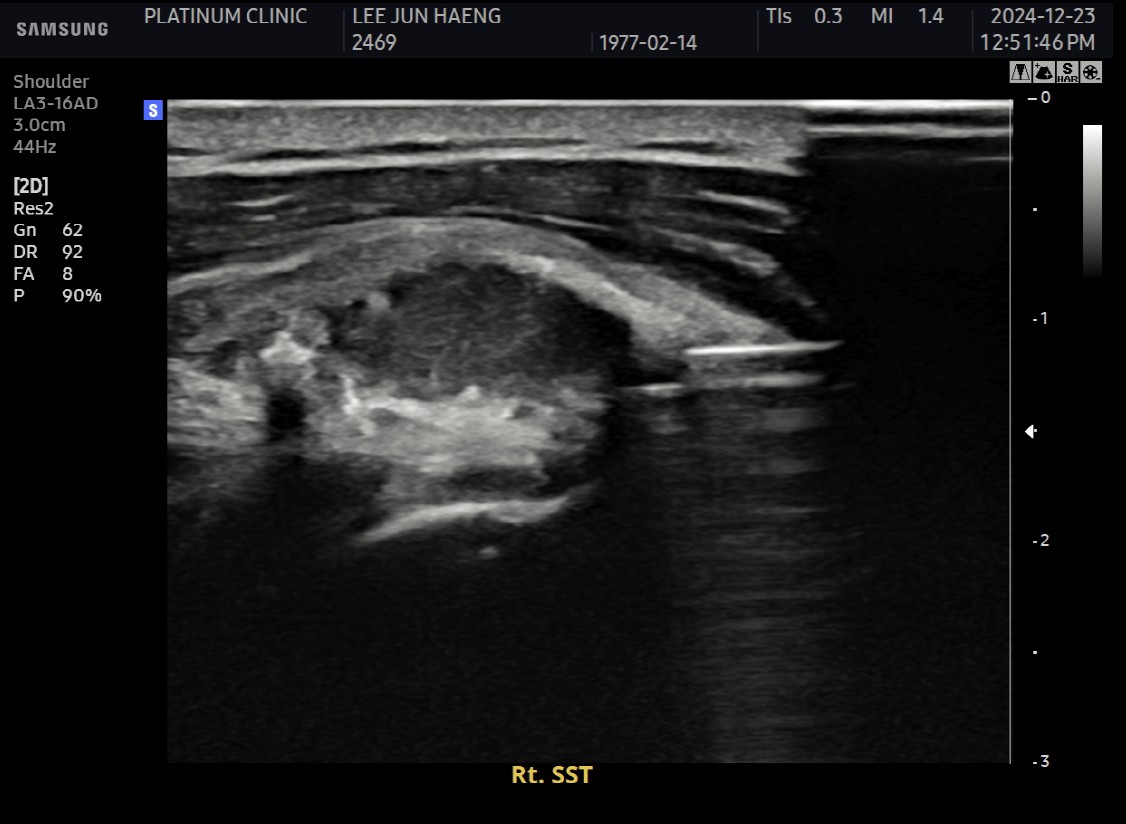

진단:

X-ray: 약 1.3cm 석회 (휴지기)

초음파: 석회 주변 인대 염증 소견

석회분쇄흡입술 시행

시술 시간: 35분

시술 직후 X-ray에서 석회 완전 제거 확인